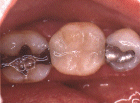

Vulling van glasionomeer vlak boven het tandvlees.

In de grote kies is, tegen de zilveramalgaamvulling aan, een compomeervulling aangebracht.